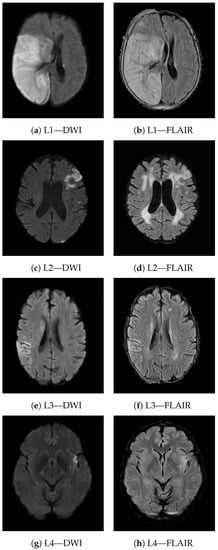

Figure 8 shows four different study cases (L1-4) demonstrating the meaning of texture heterogeneity for visual inspection. For each lesion, the axial view from both DWI and T2-FLAIR modality is reported. The lesion appears hyperintense on both imaging sequences. L1 and L2 are two examples of lesions from patients experiencing poor long-term functional outcome (90-day mRS of 6 and 5 respectively). L1 is a very severe case; the extension of the lesion is quite large, involving both GM and WM and presenting PH1 hemorrhage. L2 is less extensive compared to L1, although it too involves both GM and WM. Patients with worse outcomes present more heterogeneous lesions, often involving both GM and WM. In the presence of hemorrhage, heterogeneity in terms of radiomic features is even higher (e.g., texture heterogeneity measured in terms of Dependence non uniformity normalized—GLDM on DWI was 0.23 and 0.13 in L1 and L2, respectively). On the other hand, in patients that achieved functional independence (e.g., L3 and L4 presented a 90-day mRS of 2 and 0, respectively), the lesions were less heterogeneous (texture heterogeneity in terms of Dependence non uniformity normalized—GLDM on DWI of 0.08 and 0.04, respectively), and mostly involved GM areas.

Another interesting aspect that can be captured by texture features is the involvement of white matter (WM) and gray matter (GM) in the ischemic lesion. Both GM and WM can be affected by ischemic stroke, as they need a constant supply of oxygen and glucose. However, the collateral circulation in WM is reduced compared to GM and the reduced blood supply makes WM highly vulnerable to ischemia, leading to more rapid and severe injuries [35]. Damage in WM integrity has been shown to be related to cognitive deficits in stroke patients and worse post-stroke functional outcomes [36]. More heterogeneous lesions are more likely to involve both GM and WM, indicating more severe injuries with fewer expectations of full functional recovery. Nonetheless, the lesions in patients with a favorable functional outcome were often smaller than those that did not achieve functional independence. Very large lesions are more likely to involve both GM and WM, resulting in a more heterogeneous areas, while very small lesions are often localized in GM or WM only. Therefore, heterogeneity indirectly takes into account follow-up lesion volume, which is known to be a useful prognostic factor [37]. Despite this, when the size of the lesion is comparable (e.g., L2, L3 in Figure 8), the involvement of both GM and WM still results in higher values of heterogeneity, indicating a higher risk of poor long-term functional outcome.

Figure 8. Axial views of DWI and T2-FLAIR scans from four different lesions (L1–L4). The lesions look hyperintense on both imaging sequences. L1 and L2 are two examples of patients with poor long-term functional outcome (90-day mRS of 6 and 5 respectively). L1 is quite extensive and presents PH1 hemorrage. Both lesions include WM and GM areas of the brain (texture heterogeneity measured in terms of Dependence non uniformity normalized—GLDM on DWI of 0.23 and 0.13, respectively). L3 and L4 instead are two examples of patients with good long-term functional outcome (90-day mRS of 2 and 0, respectively). Both lesions involve GM only (texture heterogeneity measured in terms of Dependence non uniformity normalized - GLDM on DWI of 0.08 and 0.04, respectively).